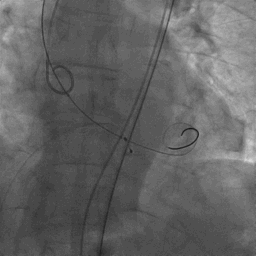

手术过程:

麻醉方式为全麻,建立静脉通路后,穿刺右侧股静脉,预埋ProGlide缝合器,食道超声指导下房间隔穿刺成功,鞘管扩张穿刺部位,沿导丝将导引导管送入左房,MitraClip调整后顺利到达二尖瓣目标位置,在X线及食道超声辅助下,将MitraClip NTR二尖瓣夹精确定位后,成功夹合二尖瓣A2-P2区,超声显示反流明显减少,多切面证实夹合组织充分,肺静脉多普勒波形由反向恢复正常,手术顺利结束,安返普通病房。

术中超声引导:

确定房间隔穿刺点:靠后

穿刺点高度测量:4.14cm

2D视图下测量大鞘长度2.2cm

2D视图下建立trajectory